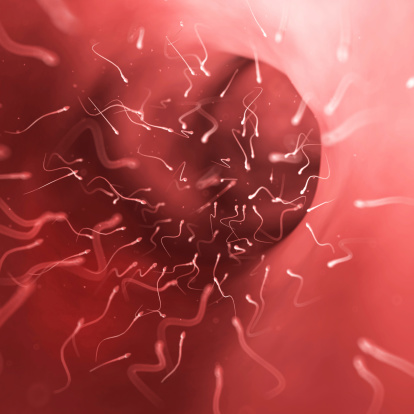

Décrite comme de la microchirurgie, cette intervention vise à récolter de façon chirurgicale des spermatozoïdes chez les hommes qui ne peuvent que recourir à un donneur ou à envisager l’adoption lorsqu’ils veulent un enfant, comme l’explique Ali Dabaja, le directeur du centre de médecine reproductive du Henry Ford Health System.

Les candidats à ce type d’opération sont les hommes dont la semence ne comprend que très peu voire aucun spermatozoïde. Cette pathologie s’appelle l’azoospermie non obstructive et touche 1% de la population masculine, et 10% des hommes qui recourent à des traitements anti-stérilité.

Cette intervention, appelée micro-TESE en anglais, permet de procéder à une biopsie très fine afin d’aller chercher de façon chirurgicale les quelques spermatozoïdes présents dans les testicules des patients atteints d’azoospermie non obstructive. Ils peuvent ensuite être utilisés lors du processus de fécondation in vitro et aboutir à une grossesse.

« Il est nécessaire d’utiliser un microscope lors de la biopsie afin d’identifier quels tubules des testicules produisent les spermatozoïdes », et de conclure « cela nous permet d’enlever d’infimes tissus testiculaires pour améliorer la récolte de spermatozoïdes ».